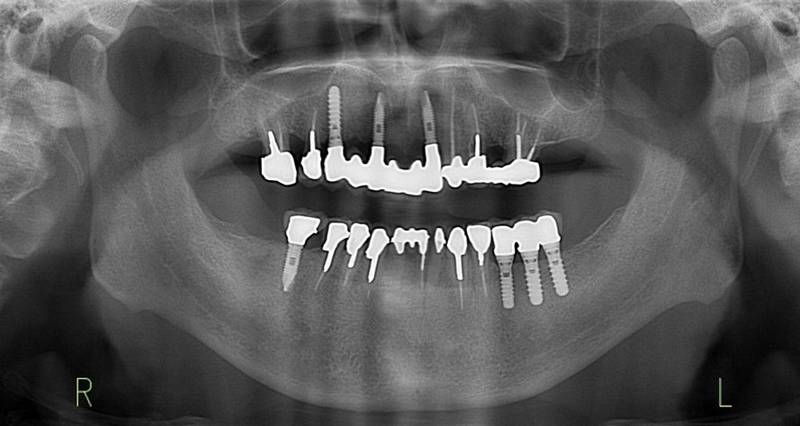

術前パノラマレントゲン写真。根の周りが黒くなり、骨がなくなっていることがわかります

術前。すべての歯が歯周病の末期状態でブリッジ全体がうごいて噛めないとの訴え。右上の犬歯が腫れていました

固定式のブリッジが入っていましたが歯周病で動いています

下顎前歯部には歯石の沈着がみられます